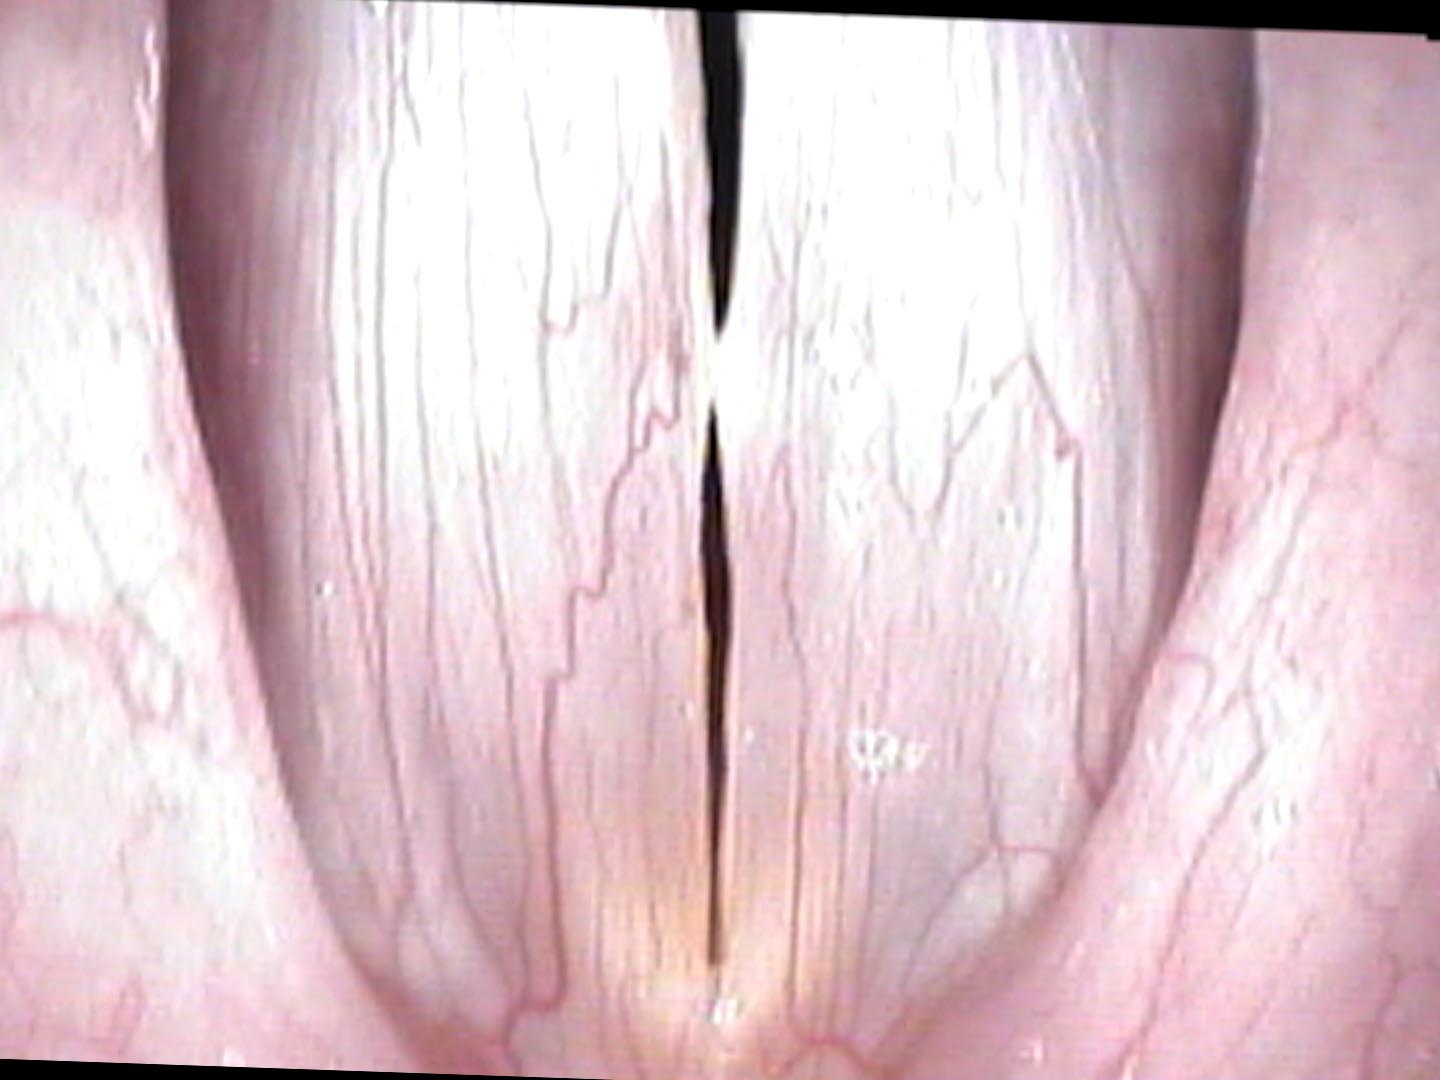

Classical singers have unusually precise awareness of their voices, which is why they are often the first to detect even small swellings. On swelling testing, the onset delay falls squarely in her professional singing range — the pitches she needs most. On endoscopy, bilateral swellings are present, modest in size but strategically positioned to silence exactly the pianissimo high notes her students expect her to demonstrate.